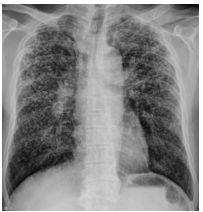

2.

8.右胸痛 3 個月